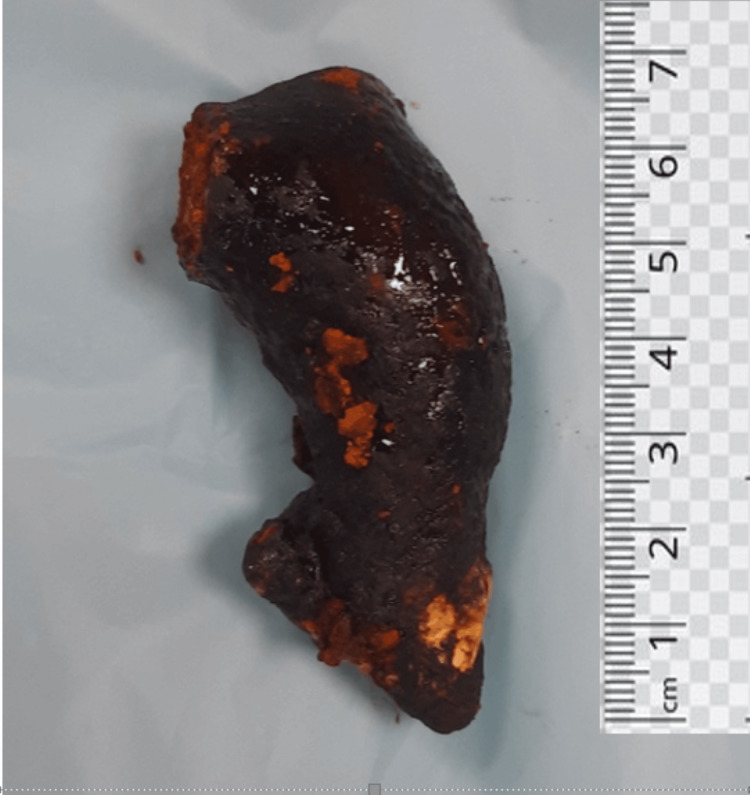

Two stay sutures were taken over the choledochal cyst wall laterally. Bile aspirated from the cyst and sent for culture/sensitivity. Choledochotomy was made and bile was aspirated (Figure 4). Giant calculi of approximately 7 cm x 3 cm were retrieved from the CDC (Figure 5). Distal dissection of the intrapancreatic portion was done till ~5 mm proximal to the tapered end. The distal end was transacted and oversewn using PDS 4-0 suture in a double layer. The proximal end was transacted 1 cm distal to the hilum. The cyst wall was sent for histopathology. Proximal jejunum was transacted ~30 cm distal to DJ flexure using a linear cutting blue 60 mm stapler. Cut ends oversewn using prolene 4-0 in a continuous manner. Opening made in transverse mesocolon and distal jejunal limb was delivered in retrocolic fashion. Tension-free end-to-side hepaticojejunostomy was done using prolene 4-0 sutures in an interrupted fashion. A bile leak was noticed from the anastomotic site and two separate sutures were taken at the leak site. Saline wash was given and a 32 Fr abdominal drain was placed in subhepatic space. The side-to-side jejuno-jejunal anastomosis was done using double-layered anastomosis in a continuous fashion (outer layers with prolene 4-0 and inner layers with vicryl 3-0). The postoperative period of the patient was uneventful. The drain was removed on postoperative day 3 and the patient was discharged on postoperative day 7.